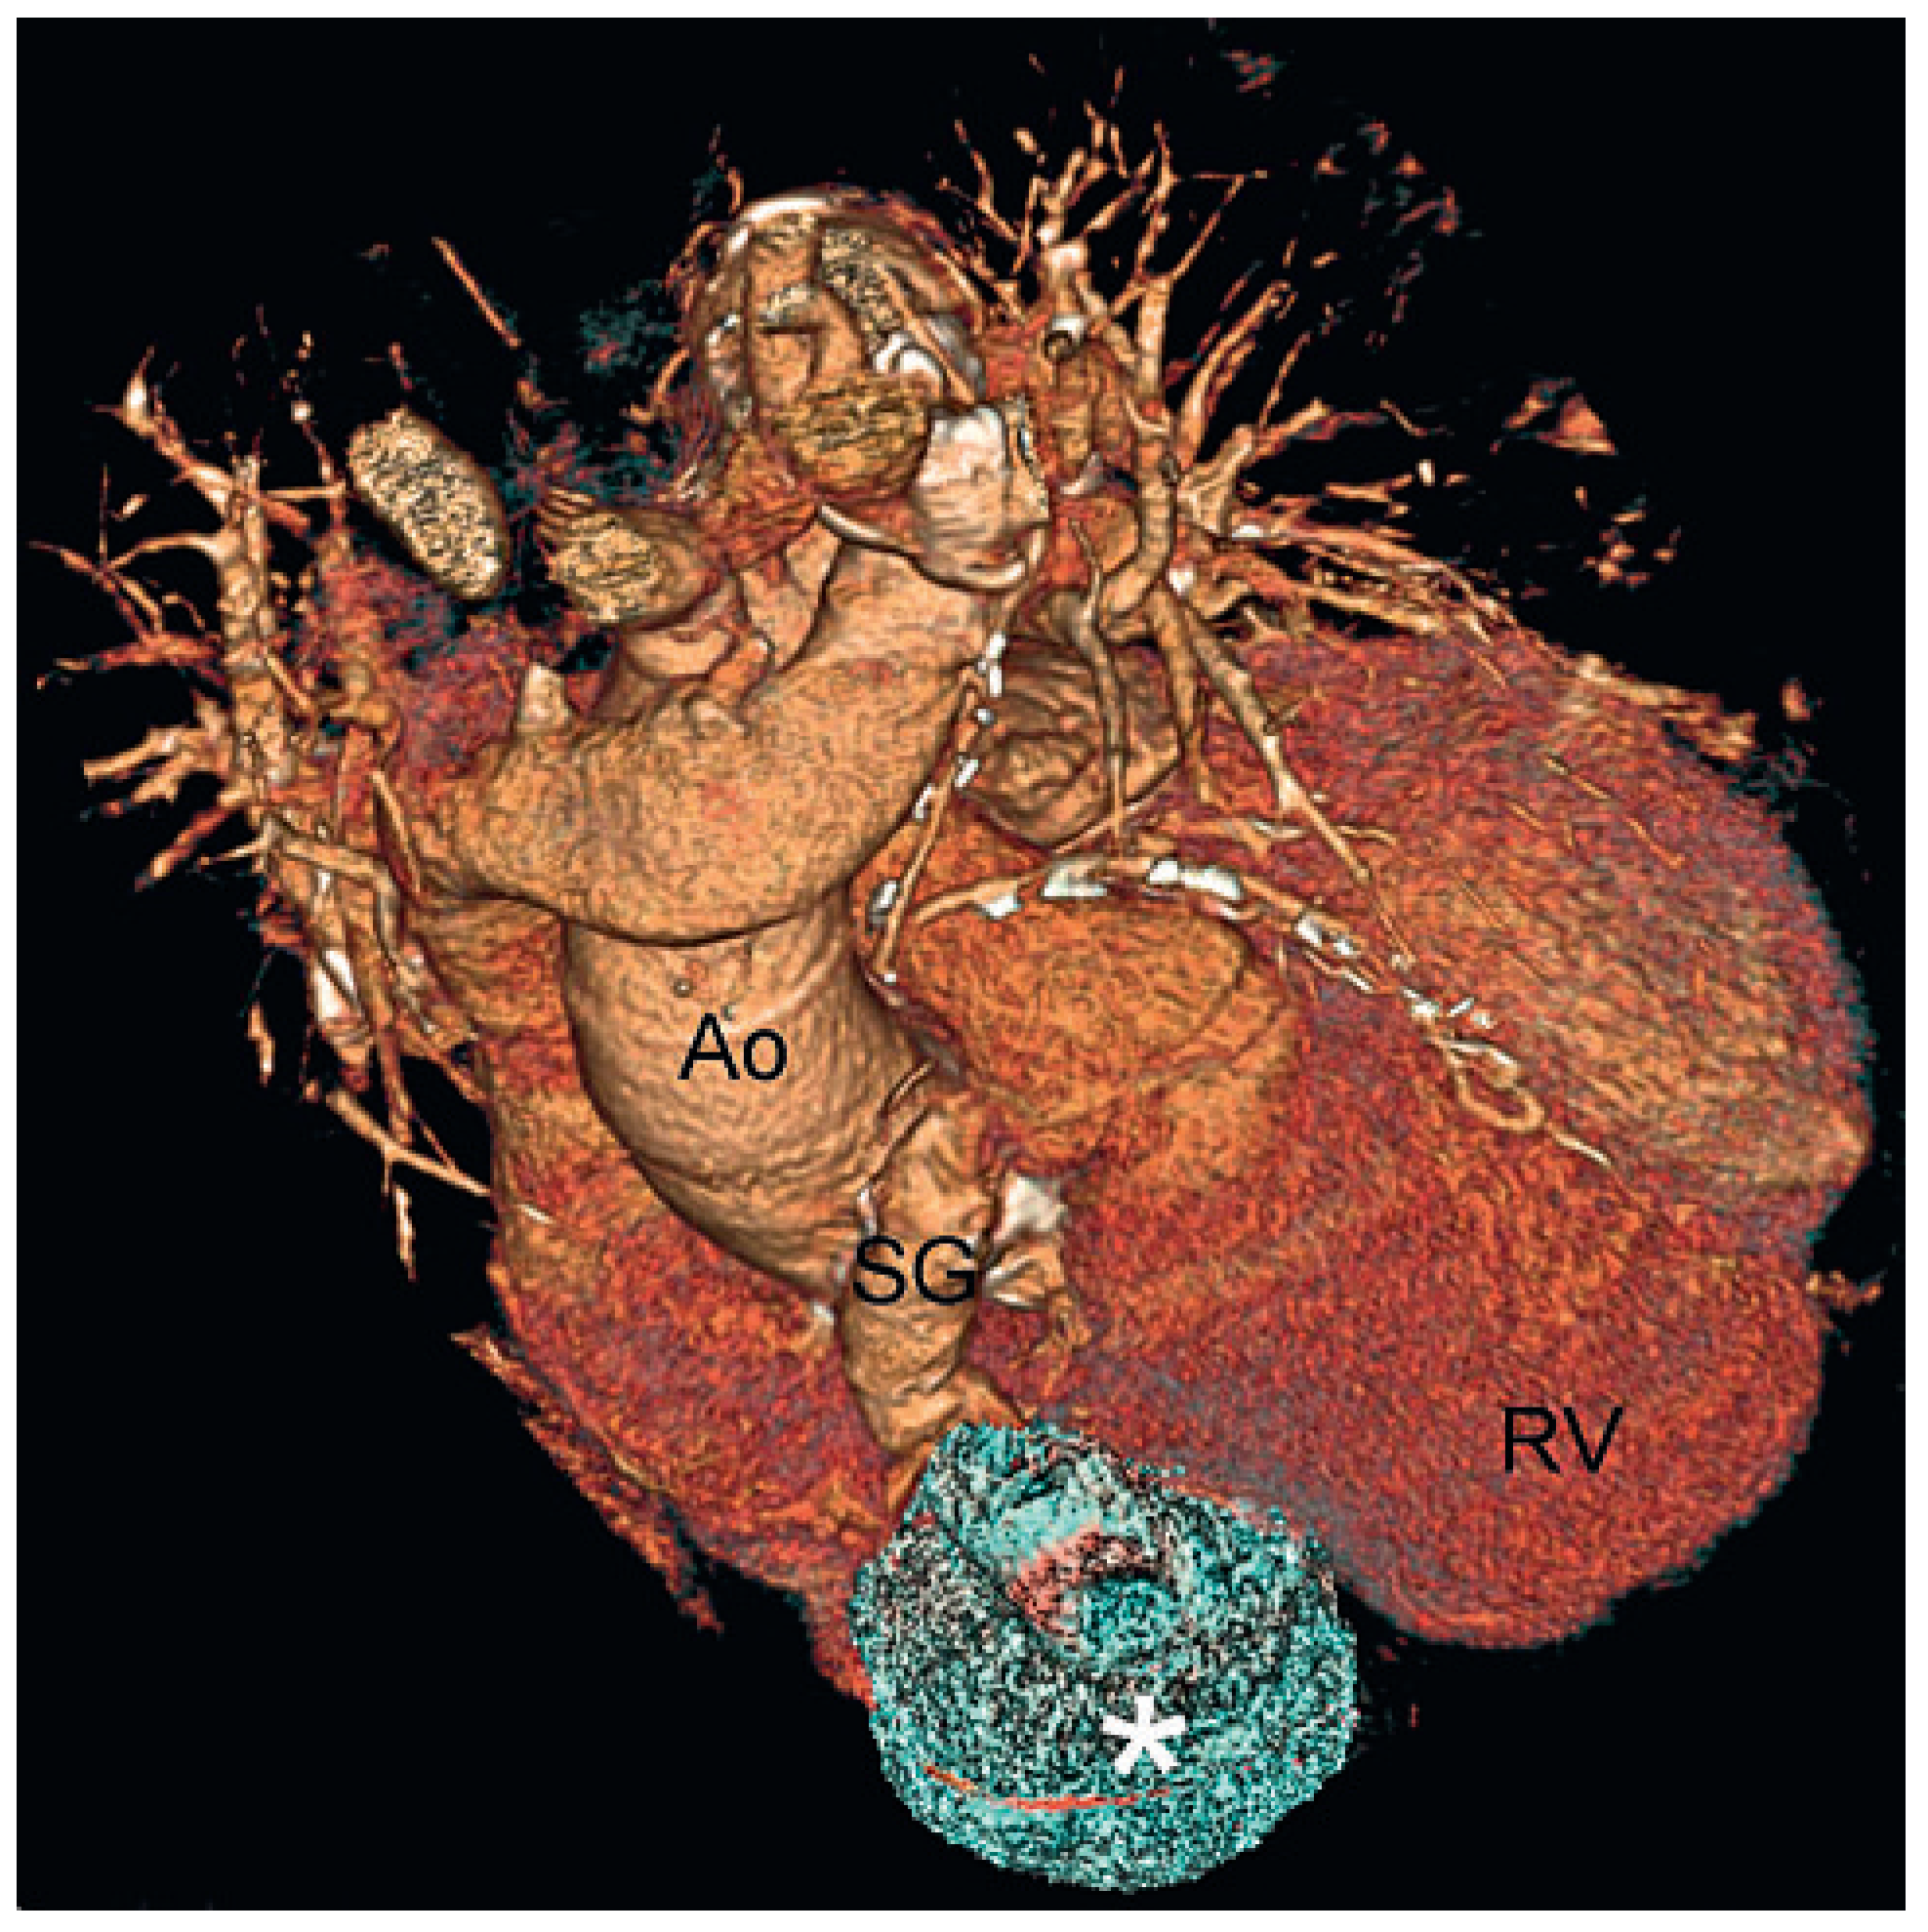

A Giant Saphenous Vein Graft Aneurysm Compressing the Right Cavities